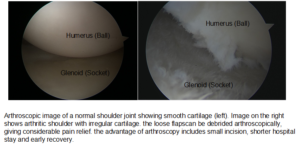

Arthroscopy: Cases of mild glenohumeral arthritis may be treated with arthroscopy, During arthroscopy, the surgeon inserts a small camera, called an arthroscope, into the shoulder joint. The camera displays pictures on a television screen, and the surgeon uses these images to guide miniature surgical instruments.

Cases of mild glenohumeral arthritis may be treated with arthroscopy, During arthroscopy, the surgeon inserts a small camera, called an arthroscope, into the shoulder joint. The camera displays pictures on a television screen, and the surgeon uses these images to guide miniature surgical instruments.

Because the arthroscope and surgical instruments are thin, the surgeon can use very small incisions (cuts), rather than the larger incision needed for standard, open surgery.

During the procedure, your surgeon can debride (clean out) the inside of the joint. Although the procedure provides pain relief, it will not eliminate the arthritis from the joint. If the arthritis progresses, further surgery may be needed in the future.